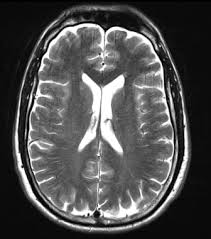

T2 Weighted Imaging

T2 is good for detecting pathologies such as cysts

Water is bright

Fat is grey

Applications:

T2 focuses on pathology, making fluids bright, which is ideal for visualizing inflammation, edema, and certain lesions